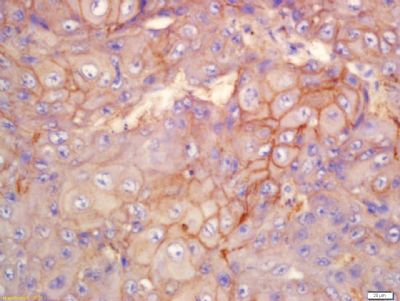

| 产品图片 | ![]() Sample: HUVEC (human)Cell Lysate at 40 ug Primary: Anti- Integrin Alpha V + Beta 3 (CD51+CD61) (bs-1310R) at 1/300 dilution Secondary: IRDye800CW Goat Anti-Rabbit IgG at 1/20000 dilution Predicted band size: 116 kD Observed band size: 120 kD ![]() Tissue/cell: Human laryngeal tissue; 4% Paraformaldehyde-fixed and paraffin-embedded; Antigen retrieval: citrate buffer ( 0.01M, pH 6.0 ), Boiling bathing for 15min; Block endogenous peroxidase by 3% Hydrogen peroxide for 30min; Blocking buffer (normal goat serum,C-0005) at 37℃ for 20 min; Incubation: Anti-Integrin Alpha V + Beta 3 (CD51 + CD61) Polyclonal Antibody, Unconjugated(bs-1310R) 1:200, overnight at 4°C, followed by conjugation to the secondary antibody(SP-0023) and DAB(C-0010) staining ![]() Tissue/cell: Human lung cancer tissue; 4% Paraformaldehyde-fixed and paraffin-embedded; Antigen retrieval: citrate buffer ( 0.01M, pH 6.0 ), Boiling bathing for 15min; Block endogenous peroxidase by 3% Hydrogen peroxide for 30min; Blocking buffer (normal goat serum,C-0005) at 37℃ for 20 min; Incubation: Anti-Integrin Alpha V + Beta 3 (CD51 + CD61) Polyclonal Antibody, Unconjugated(bs-1310R) 1:200, overnight at 4°C, followed by conjugation to the secondary antibody(SP-0023) and DAB(C-0010) staining ![]() cell: mouse lung. Incubation: Avoid light, at 4°C for 40 minutes. Red line: Blank control (mouse lung cells),2X10^6/ml, at 4°C for 40 minutes. Green line: (primary antibody) Integrin Alpha V + Beta 3 (CD51+CD61) (bs-1310R), (secondary antibody)Goat Anti-rabbit IgG/FITC (bs-0295G-FITC), 1:00, at 4°C for 40 minutes. ![]() Tissue/cell: rat brain tissue; 4% Paraformaldehyde-fixed and paraffin-embedded; Antigen retrieval: citrate buffer ( 0.01M, pH 6.0 ), Boiling bathing for 15min; Block endogenous peroxidase by 3% Hydrogen peroxide for 30min; Blocking buffer (normal goat serum,C-0005) at 37℃ for 20 min; Incubation: Anti-Integrin Alpha V + Beta 3(CD51+CD61) Polyclonal Antibody, Unconjugated(bs-1310R) 1:200, overnight at 4°C, followed by conjugation to the secondary antibody(SP-0023) and DAB(C-0010) staining ![]() Blank control: U937(blue). Primary Antibody: Rabbit Anti-Integrin Alpha V + Beta 3 (CD51+CD61) antibody(bs-1310R), Dilution: 1μg in 100 μL 1X PBS containing 0.5% BSA; Isotype Control Antibody: Rabbit IgG(orange) ,used under the same conditions ); Secondary Antibody: Goat anti-rabbit IgG-PE(white blue), Dilution: 1:200 in 1 X PBS containing 0.5% BSA. Protocol The cells were fixed with 2% paraformaldehyde (10 min). Primary antibody (bs-1310R, 1μg /1x10^6 cells) were incubated for 30 min on the ice, followed by 1 X PBS containing 0.5% BSA + 10% goat serum (15 min) to block non-specific protein-protein interactions. Then the Goat Anti-rabbit IgG/PE antibody was added into the blocking buffer mentioned above to react with the primary antibody at 1/200 dilution for 30 min on ice. Acquisition of 20,000 events was performed. ![]() Cell: MCF-7 Concentration:1:100 Host/Isotype:Rabbit/IgG Flow cytometric analysis of Rabbit IgG isotype control (Cat#: bs-1310R) on MCF-7(green) compared with control in the absence of primary antibody (blue) followed by Alexa Fluor 488-conjugated goat anti-rabbit IgG(H+L) secondary antibody . |